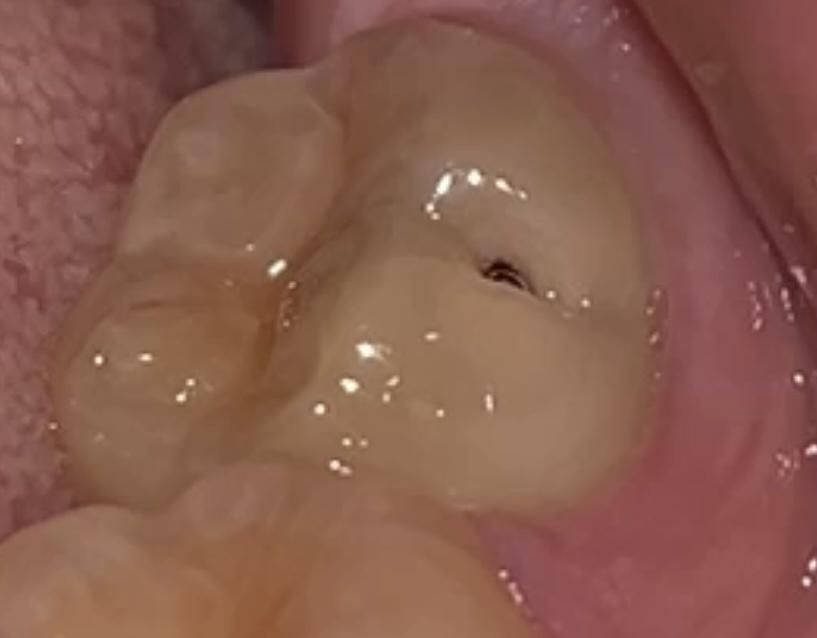

아래턱 양쪽 맨 안쪽 어금니 (37번, 47번) 바깥쪽(볼 쪽) 옆면입니다.

교합면이나 인접면이 아니라, 바깥쪽을 향한 옆면에 명확한 까만 구멍이 뚫려 있습니다.

• 1번 째 사진